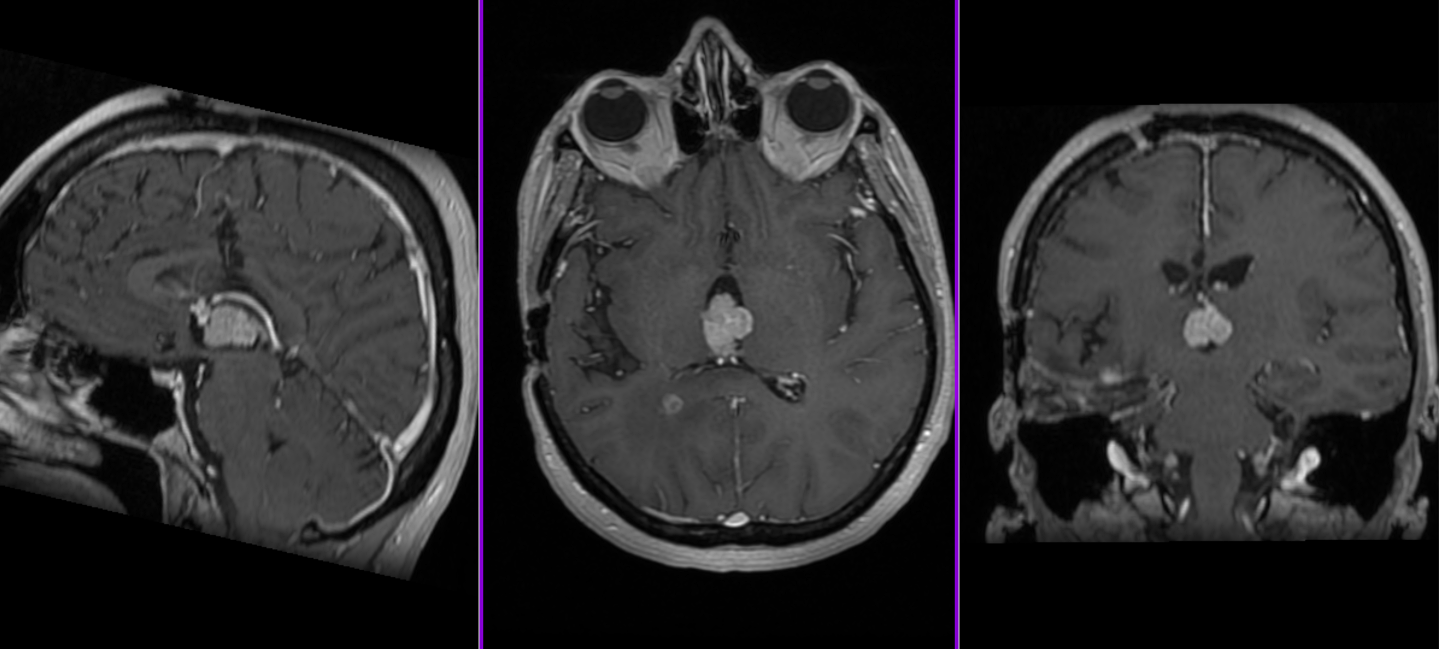

– Investigații imagistice: RMN (rezonanță magnetică) și/sau CT (tomografie computerizată), care evidențiază masa tumorală și hidrocefalia asociată

Datorită poziției profunde (ventriculii laterali sunt situați în mijlocul emisferelor cerebrale iar ventriculul III și IV în mijlocul creierului, înconjurați de structuri vitale), abordul chirurgical al acestor tumori este adesea dificil, reprezentând o provocare chiar și pentru cei mai experimentați chirurgi.